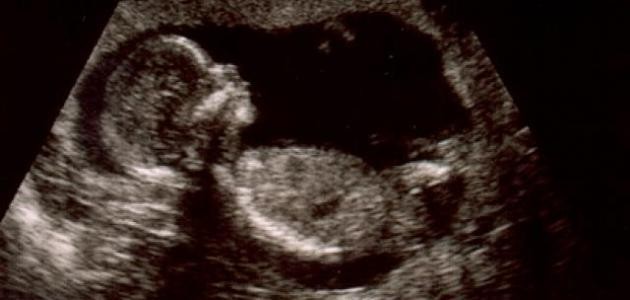

• حساب العمر من خلال قياس حجم الرحميتمكن الطبيب من التعرف على عمر الحمل من خلال قياس حجم الرحم، إذ أنه حينما يشعر الطبيب بوجود الرحم أعلى الحوض يدل ذلك على أن الحمل في قد بلغ الأسبوع الثاني عشر، بينما عقب مرور الأسبوع الثامن عشر فإن المسافة ما بين قاع الرحم وعظمة العانة بالسنتيمتر تساوي عدد أسابيع الحمل بالتقريب.بينما ببلوغ الأسبوع العشرون يصبح قاع الرحم مرتفعاً، حيث تستخدم تلك الطريقة للوصول إلى عمر الحمل بالتقريب حيث لا يمكن اعتبارها طريقة دقيقة للتعرف على عمر الجنين وعمر الحمل، وفي ذلك يوجد طرق أخرى قد تؤدي أن يصبح قاع الرحم أعلى أو أسفل مما يجب أن يكون عليه منها أن يكون وضع الجنين بالرحم غير طبيعي، أو أن تكون الأم مصابة بأحد الأورام الليفية بالرحم.[3]حساب العمر بواسطة الموجات الفوق صوتيةتعد تلك الطريقة هي الأدق في عملية حساب عمر الحمل أو مدته بدقة والمعروفة في الإنجليزية بـ(Ultrasound) ويتم اللجوء إليها غالباً في الحالة التي تكون الدورة الشهرية غير منظمة أو يصعب على الأم تذكر موعد بدايتها الأخير، كما تعرف تلك الطريقة بالمسح الضوئي حينما يقوم الطبيب بمسح الجنين بدايةً من رأسه وحتى قدميه.الجدير بالذكر أن أنسب وقت يمكن خلاله إجراء الكشف بالموجات الفوق الصوتية في الفترة ما بين الأسابيع (الثامن حتى الثامن عشر) بالحمل، ويتم إجراء ذلك الفحص بواسطة جهاز صغير الحجم يعرف بالمحول (Transducer) إذ يقوم بإرسال الموجات الفوق صوتية والتي ترتد إلى جسم الجنين ثم يعمل على تحويلها ثانية إلى صورة جنين عبر جهاز الحاسب الآلي لكي يصبح من الممكن ظهورها بجهاز التلفاز، كذلك يمكن قياس حجم رأس الطفل بواسطة تلك الطريقة وبطنه وعظام الفخذين، والتعرف أيضاً على نمو الجنين وصحته.[4]،[5]